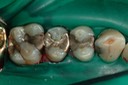

Matt Dodson #3 pre-op

Matt Dodson #3 caries removal